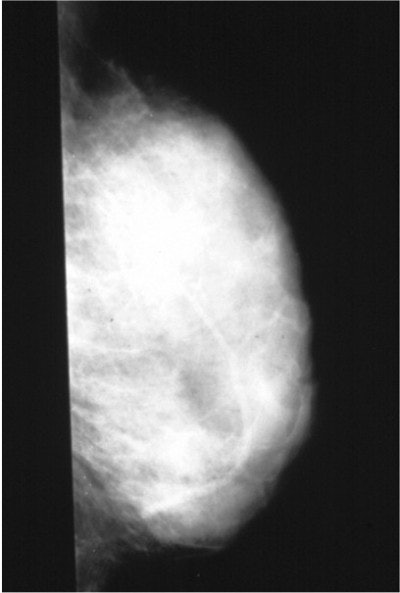

![]() |

| Mammogram of a dense breast, which illustrates the difficulty of detecting a non-deforming, non-calcified small cancer (white) in a background of dense (white) glandular tissue. Image courtesy of Dr. Thomas Kolb. |